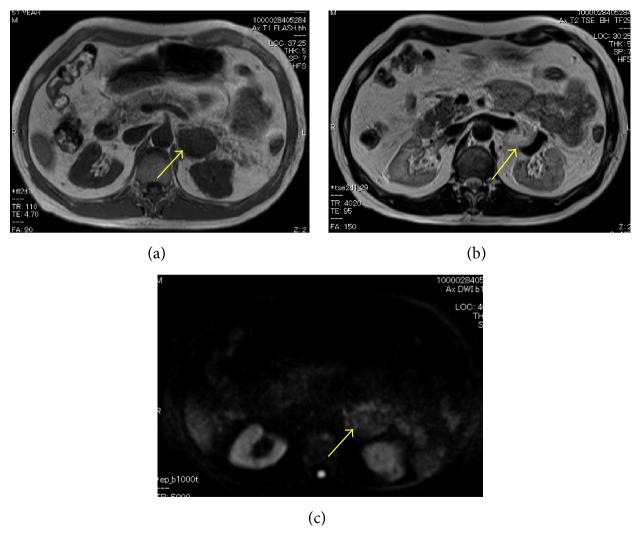

A 52-year-old man was referred to our department for further examination of his left retroperitoneal tumor. He had received hemodialysis due to chronic renal failure resulting from membranous nephropathy. Computed tomography revealed a mass around his left hilum. Magnetic resonance imaging (MRI) and positron-emission tomography (PET)-CT were unable to confirm or deny malignancy, and tumor markers, including CEA and CA19-9, showed slight elevation. His tumor grew from 38 mm to 54 mm in diameter in 7 months of follow-up. We therefore planned retroperitoneal tumor resection with left nephrectomy. Histopathologically, hyperplastic small vessels with hemorrhaging and denaturation were seen. The endothelial cells showed no variants or division of the nucleus. Based on this diagnosis, no further therapy was performed. He has had no recurrence in the eight months since the surgery.

一名52岁男性因左腹膜后肿瘤前来我院进一步检查。他因膜性肾病导致的慢性肾衰竭接受血液透析。计算机断层扫描显示左肾门周围有一个肿块。磁共振成像(MRI)和正电子发射断层扫描(PET)-CT无法确定肿块是否为恶性,包括癌胚抗原(CEA)和糖类抗原19-9(CA19-9)在内的肿瘤标志物略有升高。在7个月的随访中,他的肿瘤直径从38毫米增长到了54毫米。因此,我们计划行腹膜后肿瘤切除术并切除左肾。组织病理学检查可见增生的小血管伴出血和变性。内皮细胞未见核异型或核分裂。基于这一诊断,未进行进一步治疗。术后八个月他未出现复发。